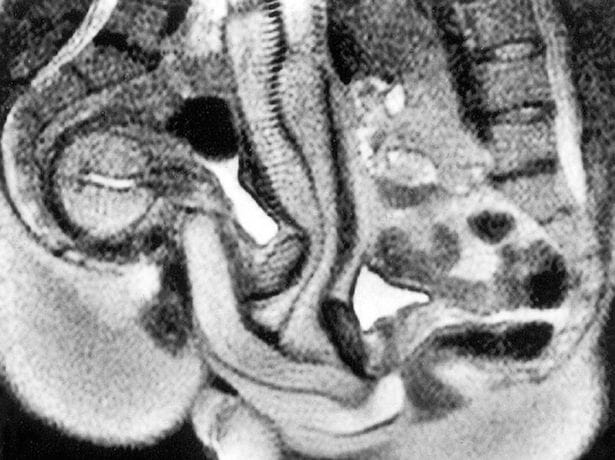

وطن– كشفت فحوصات التصوير بالرنين المغناطيسي لزوجين من جنسين مختلفين يمارسان الجنس، أنّ القضيب المنتصب لا يكون في الحقيقة صلبًا، وبدلاً من ذلك ينحني ويأخذ شكل تجاويف المهبل.

وكشفت التجرية عن أكبر نتيجتين، هما: أنّ المهبل ليس مستقيماً، وأن القضيب يمكن أن ينحنيَ لاستيعاب الانحناء الطبيعي للمهبل.

وكشفت عمليات المسح التي أُجريت على إيدا وجوب، في أثناء ممارسة الجنس -وهي الأولى من نوعها- أنّ القضيب المنتصب يمكن أن يصنع نفسه على شكل قطعة مرنة ملتوية، مما يعني أنه يمكن أن ينحني إلى الداخل على شكل جسم المرأة، دون التسبب في أي ألم للرجل.

وتحدّت هذه النتائج الاعتقاد الراسخ -والذي يمكن أن يعود إلى زمن ليوناردو دافنشي- بأن قضيب الرجل يذهب مباشرة إلى مهبل المرأة، ويخرج مباشرة مرة أخرى، وأن المهبل على شكل أسطوانة.